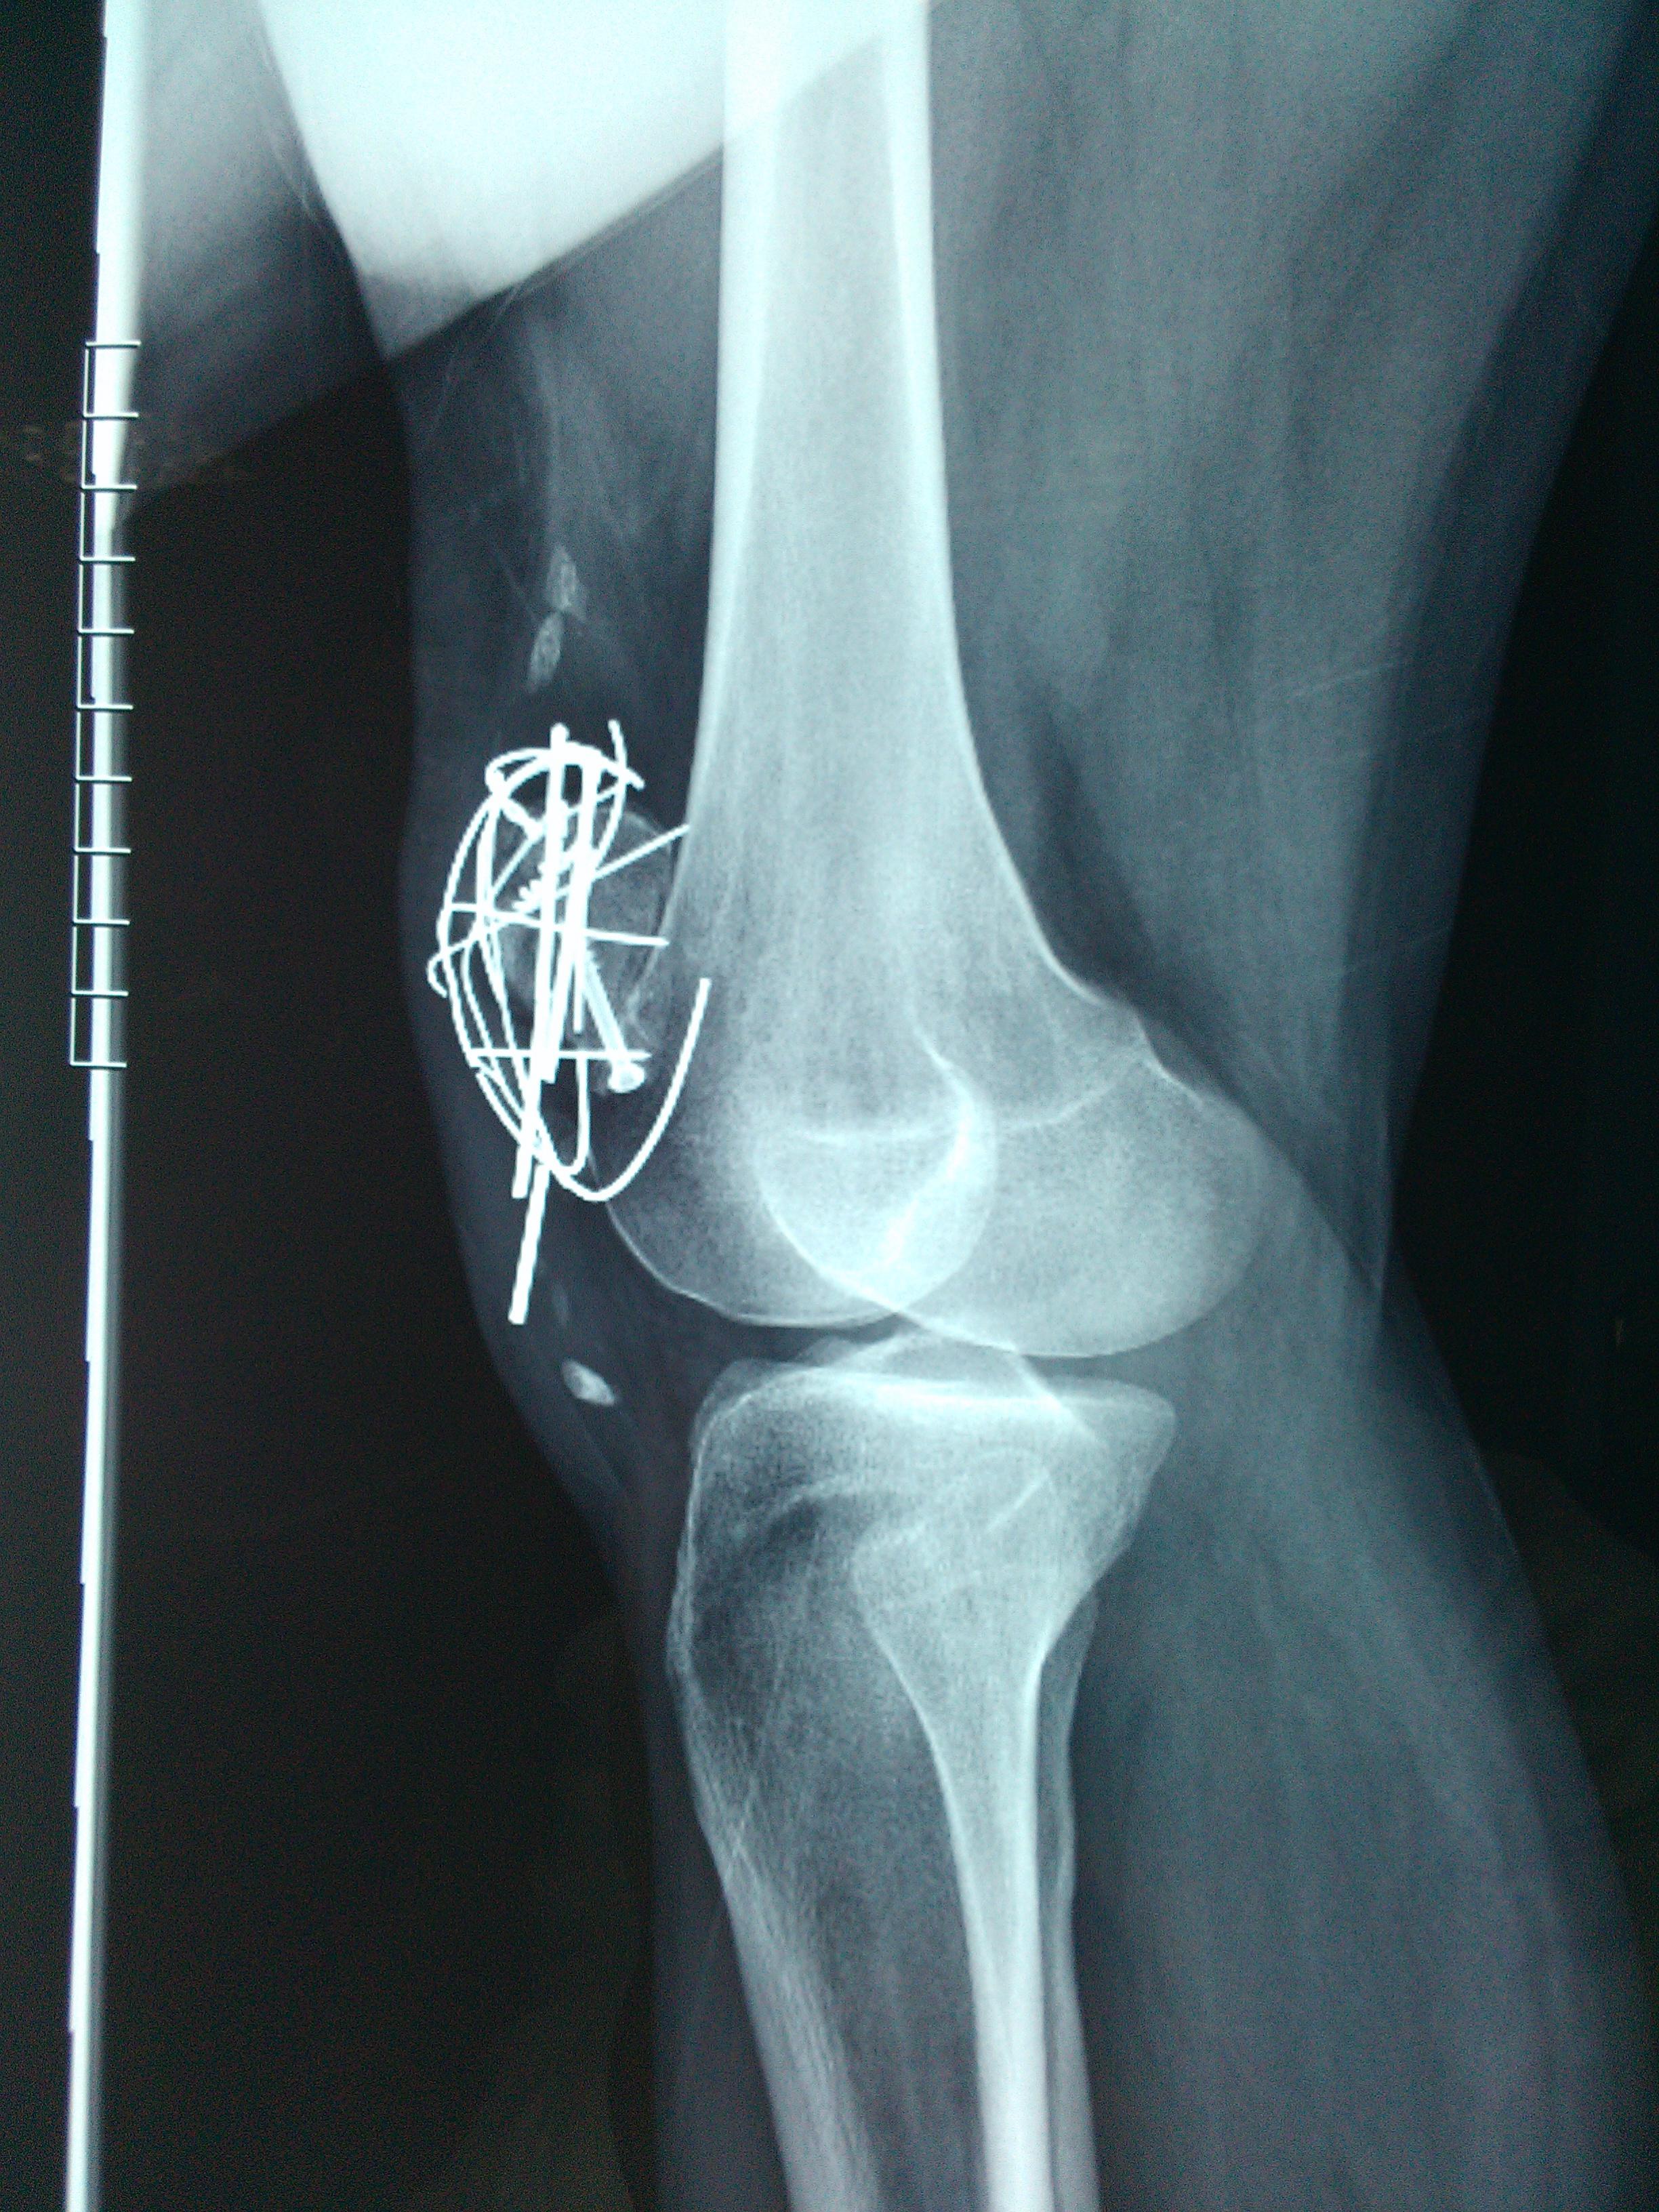

患者男性,34岁,左髌骨粉碎型骨折术后2年余。今日来诊诉局部轻微外伤后疼痛。查体:髌骨下缘钢钉有触痛,(但当时手术医生嘱咐:“无需内固定取出”……)请问各位专家同道:可以剪断髌骨下缘疼痛的钢钉吗?

髌骨内固定术后,部分内固定物断裂,不知道膝关节活动的怎么样,如果可以的话,还是建议取出全部的内固定物,但是术前一定要告知手术创伤较大,也可能部分内固定物无法取出。